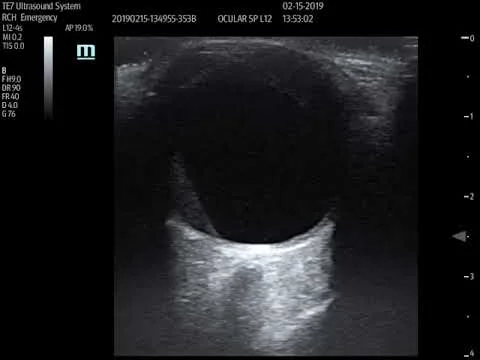

Stent with occluded R CFA